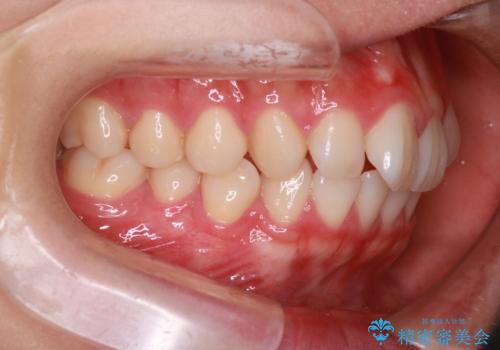

スペースを作るために顎間ゴムを使用して、奥歯の遠心移動をおこない配列しました。

奥歯の遠心移動を行うことで、犬歯関係も良い状態に仕上げることができました。